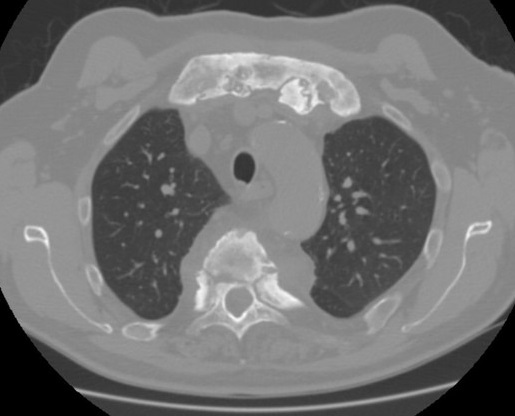

Aspect d'élargissement et

épaississement du cartilage au niveau de articulation

sternocostale gauche et oedème de la moelle

osseuse dans sous-chondral . Image radiologique TDM

coupe axial d'une syndrome Tierzt gauche du thorax